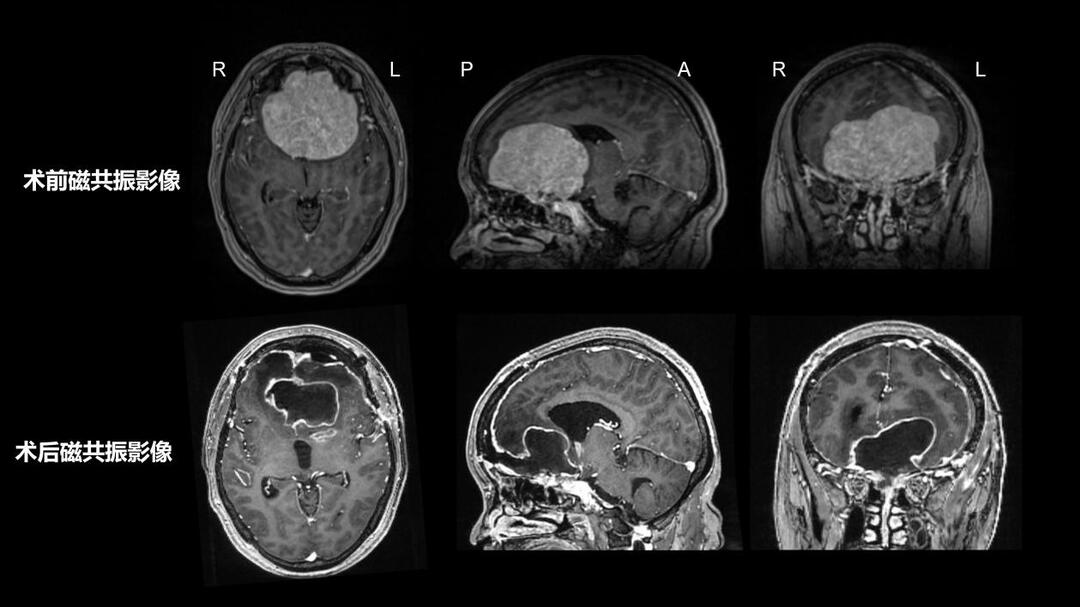

怀着对健康的渴望与对高水平医疗的信任,黎女士辗转打听,最终慕名来到湘雅医院,找到神经外科李学军教授团队。经过进一步检查发现,其前颅底肿瘤体积达7.4cm×7.3cm×7cm,额叶、下丘脑、穹隆、三脑室及双侧脑室严重受压,肿瘤甚至向筛窦、鼻腔内生长;左额部还有一枚1.9cm×1.5cm×1.3cm的肿瘤;前颅底骨质已被破坏,双侧大脑前动脉被肿瘤包绕,双侧颈内动脉及大脑中动脉也受压移位。

4月2日,由李学军教授主刀,为黎女士成功实施了前颅底及左额部病变切除术。团队巧妙设计一个切口,同时显露两个肿瘤,秉持“毫米级精细操作”原则,逐层分离肿瘤组织,谨慎剥离与神经、血管粘连的部位,精准处理肿瘤基底硬脑膜。

两小时的显微镜下精细操作,不仅彻底清除了病灶,更最大程度减少了对正常脑组织的牵拉与损伤,从根源上降低了复发风险。同时,团队还为她完成了颅底修复重建,为后续康复打下坚实基础。

术后,黎女士未出现任何神经功能缺损症状,术前的头痛、乏力、记忆力差等不适明显好转,各项指标恢复正常,整体康复效果远超预期。